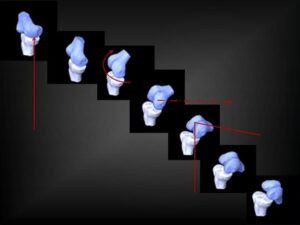

Η κάμψη – έκταση προεξάρχει φυσικά, ωστόσο με όρους εμβιομηχανικής περιγράφεται ως «κύλιση και ολίσθηση» ή «roll and glide/slide». (εικόνα 3 )